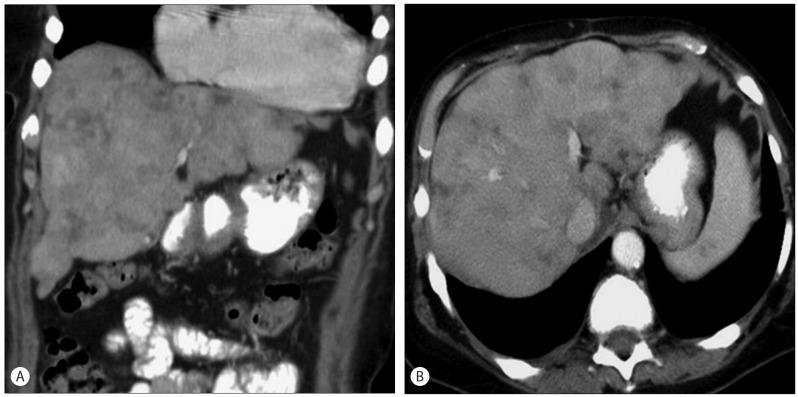

Treating patients undergoing chemotherapy who display findings of liver toxicity, requires a solid understanding of these medications. It is important for any clinician to have an index of suspicion for liver toxicity and be able to recognize it, even on imaging. Cancer chemotherapy has evolved, and newer medications that target cell biology have a different pattern of liver toxicity and may differ from the more traditional cytotoxic agents. There are several hepatic conditions that can result and keen clinical as well as radiographic recognition are paramount. Conditions such as sinusoidal obstructive syndrome, steatosis, and pseudocirrhosis are more commonly associated with chemotherapy. These conditions can display clinical signs of acute hepatitis, liver cirrhosis, and even liver failure. It is important to anticipate and recognize these adverse reactions and thus appropriate clinical action can be taken. Often times, patients with these liver manifestations can be managed with supportive therapies, and liver toxicity may resolve after discontinuation of chemotherapy.

治疗出现肝毒性表现的化疗患者,需要对这些药物有扎实的了解。任何临床医生都必须对肝毒性保持怀疑指数,并能够识别它,即使是通过影像学手段。癌症化疗已经发展,靶向细胞生物学的新型药物具有不同的肝毒性模式,可能与更传统的细胞毒性药物有所不同。有几种肝脏疾病可能由此引发,敏锐的临床及影像学识别至关重要。诸如窦性阻塞综合征、脂肪变性和假性肝硬化等病症更常与化疗相关。这些病症可表现出急性肝炎、肝硬化甚至肝衰竭的临床体征。预见并识别这些不良反应很重要,这样才能采取适当的临床行动。通常,有这些肝脏表现的患者可以通过支持性疗法进行治疗,并且肝毒性可能在化疗停药后消退。